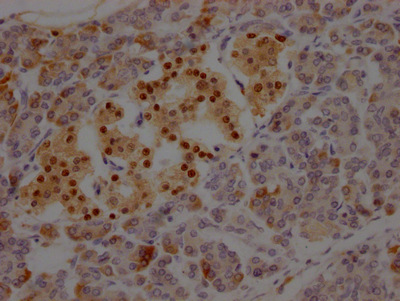

IHC image of CSB-RA941933A0HU diluted at 1:100 and staining in paraffin-embedded human pancreatic tissue performed on a Leica BondTM system. After dewaxing and hydration, antigen retrieval was mediated by high pressure in a citrate buffer (pH 6.0). Section was blocked with 10% normal goat serum 30min at RT. Then primary antibody (1% BSA) was incubated at 4℃ overnight. The primary is detected by a Goat anti-rabbit IgG polymer labeled by HRP and visualized using 0.05% DAB.